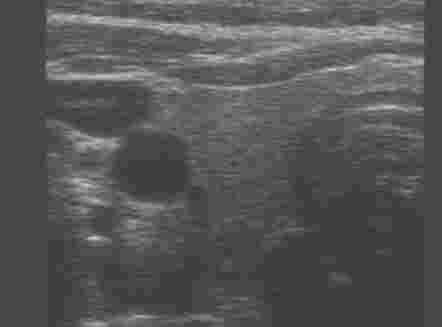

| Hals- und Gesichtsweichteile |

| Schilddrüse | |